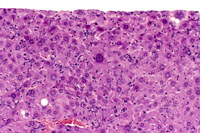

Diffuse proliferation of sinusoidal lining cells, hepatocytomegaly, and karyomegaly are evident in this liver.